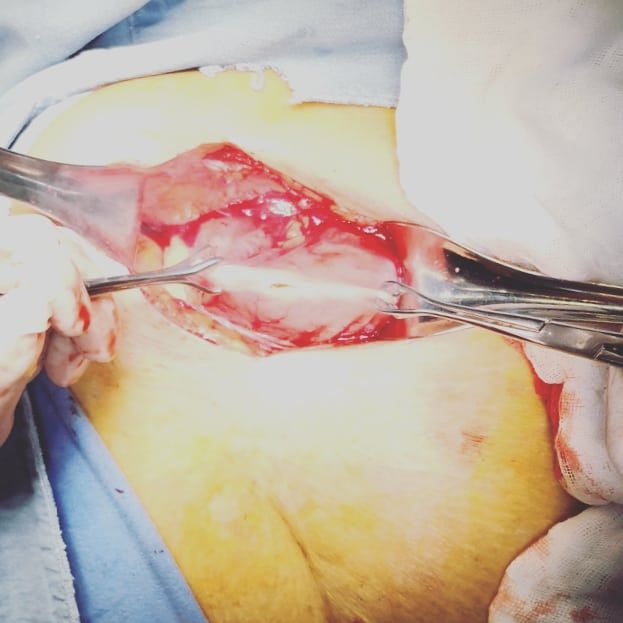

Mi experiencia abarca un espectro diverso, desde apendicitis hasta afecciones de la vesícula biliar, el colon y el recto. Como especialista en Laparoscopia, estoy dedicado a utilizar técnicas avanzadas y soluciones personalizadas para abordar las necesidades únicas de cada paciente.

• Cirugía laparoscópica

• Cirugía de vesícula y vía biliar